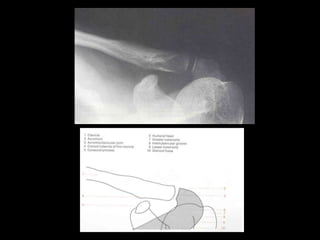

This document provides an overview of normal musculoskeletal imaging. It discusses basic x-ray concepts and densities. It then reviews normal anatomy as seen on x-rays of the skull, spine, pelvis, chest, and extremities. Key anatomical structures are labeled on example x-rays for the shoulder, hip, knee, and foot. Quizzes are included to test recognition of anatomical structures and patient age based on x-rays.